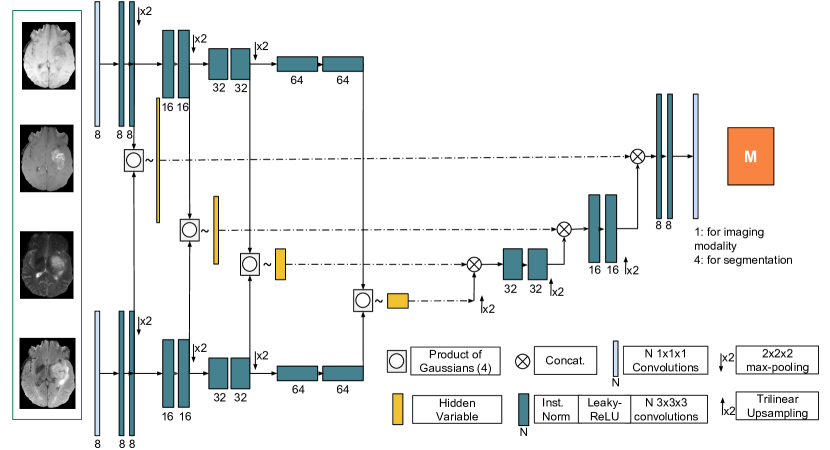

To exploit our framework we propose a novel network architecture: a 3D encoder-decoder with variational skip-connections. Our model is a mix between a 3D U-Net [10] and the MVAE [13].

In the U-net architecture, context information is extracted via the contracting path (encoder) and precise localisation is produced by the expanding part (decoder). In addition, information is captured at different levels via the skip-connections. To avoid a trivial identity function, existing auto-encoder architectures do not use skip-connections. In our case, the encoding of the latent variable is multi-modal and the imposed consistency of the latent representation creates a bottleneck. Skip-connections therefore do not allow for trivial identity mapping and can be included in our architecture.

We propose to use a multi-level latent variable to generate them. Figure 2 shows our network architecture. Unlike the existing hierarchical VAE models [11, 14], we propose a fully convolutional network. Each modality is independently encoded which produces 4 multi-scale means and variances . At each level, the means and the variances of the modalities present in the input subset are combined via the product of Gaussian defined in (4). We then decode the multi-scale latent variable for each of the modalities and the segmentation. Consequently, we have encoders and decoders. We assert that it is the first deep network which allows for missing modalities and performs 3D imaging reconstruction and segmentation in a variational manner.